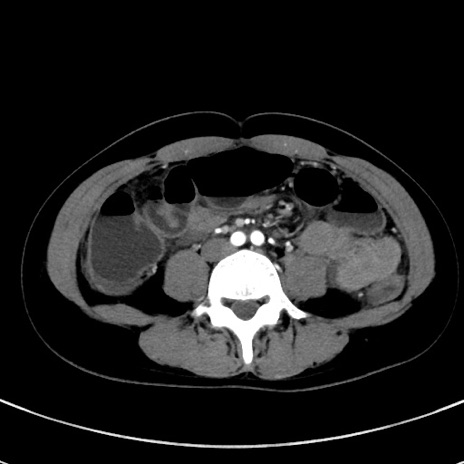

症例17(横断像)

【症例】20歳代女性

【主訴】嘔吐、下腹部痛

【現病歴】昨日夕食後に嘔吐し下腹部痛が出現。本日になっても嘔吐持続し改善しないため来院。

【身体所見】意識清明、BT 37.2℃、BP 108/67mmHg、腹部:平坦、やや硬、下腹部正中から右にかけて圧痛あり、反跳痛軽度あり、tapping pain(+)。

【データ】WBC 13600、CRP 14.94

冠状断像